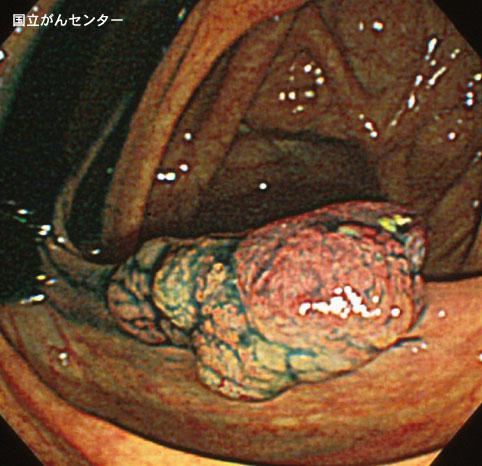

확대내시경이 유용했던 Isp형의 조기대장암(증례제시:국립 암센터)

[Image-ID:3229]

악성 상피성종양/선암

대장/상행

내시경

0형(표재형)/I형(Isp)

20~24

sm